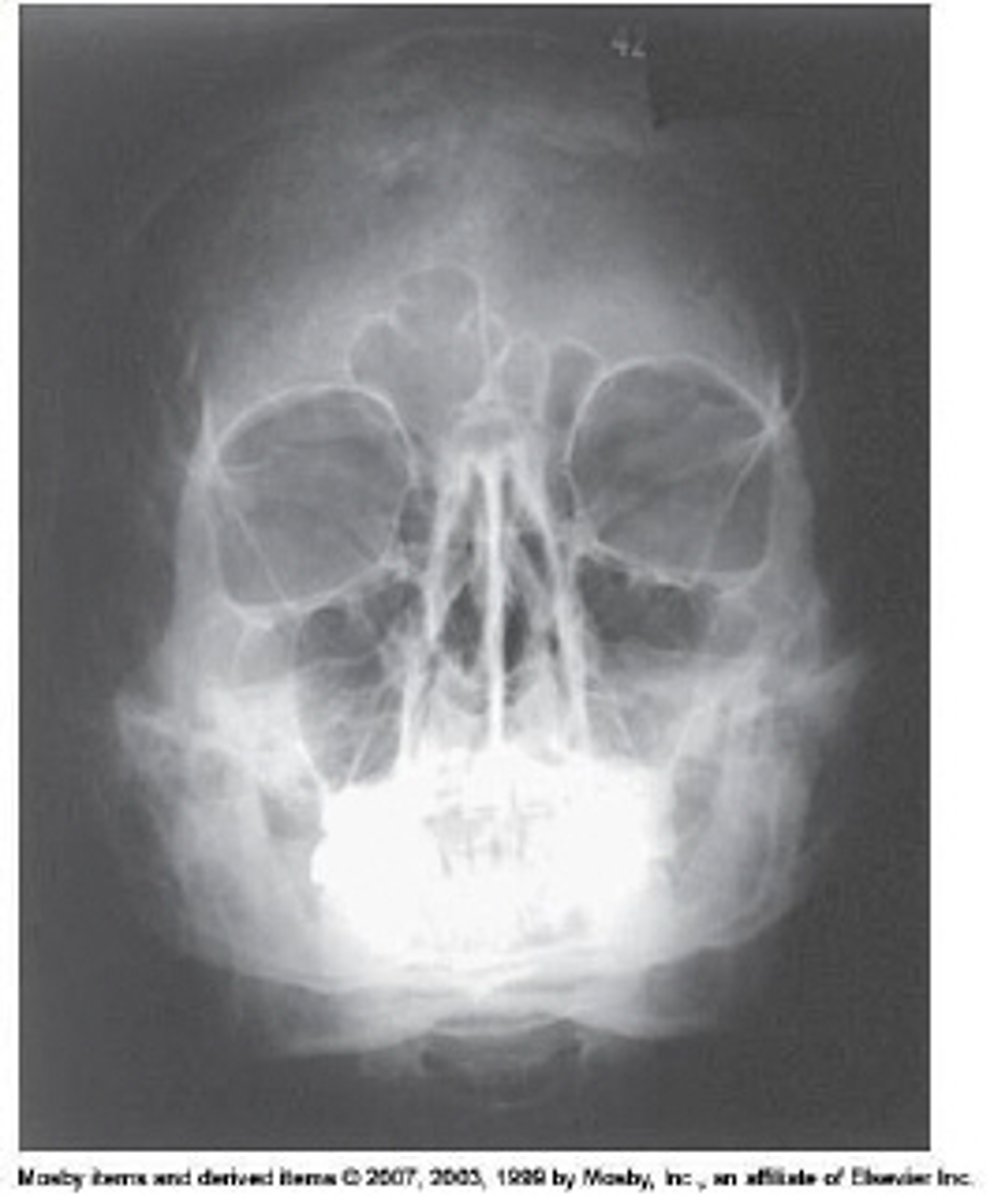

What projection and method is demonstrated?

Parietoacanthial (modified Waters)

Which of the following is(are) true regarding positioning for the Waters method for the facial bones?

1. The orbitomeatal line forms a 37-degree angle with the plane of the IR.

2. The mentomeatal line is perpendicular to the IR plane.

3. The coronal plane is perpendicular to the IR plane.

1 and 2